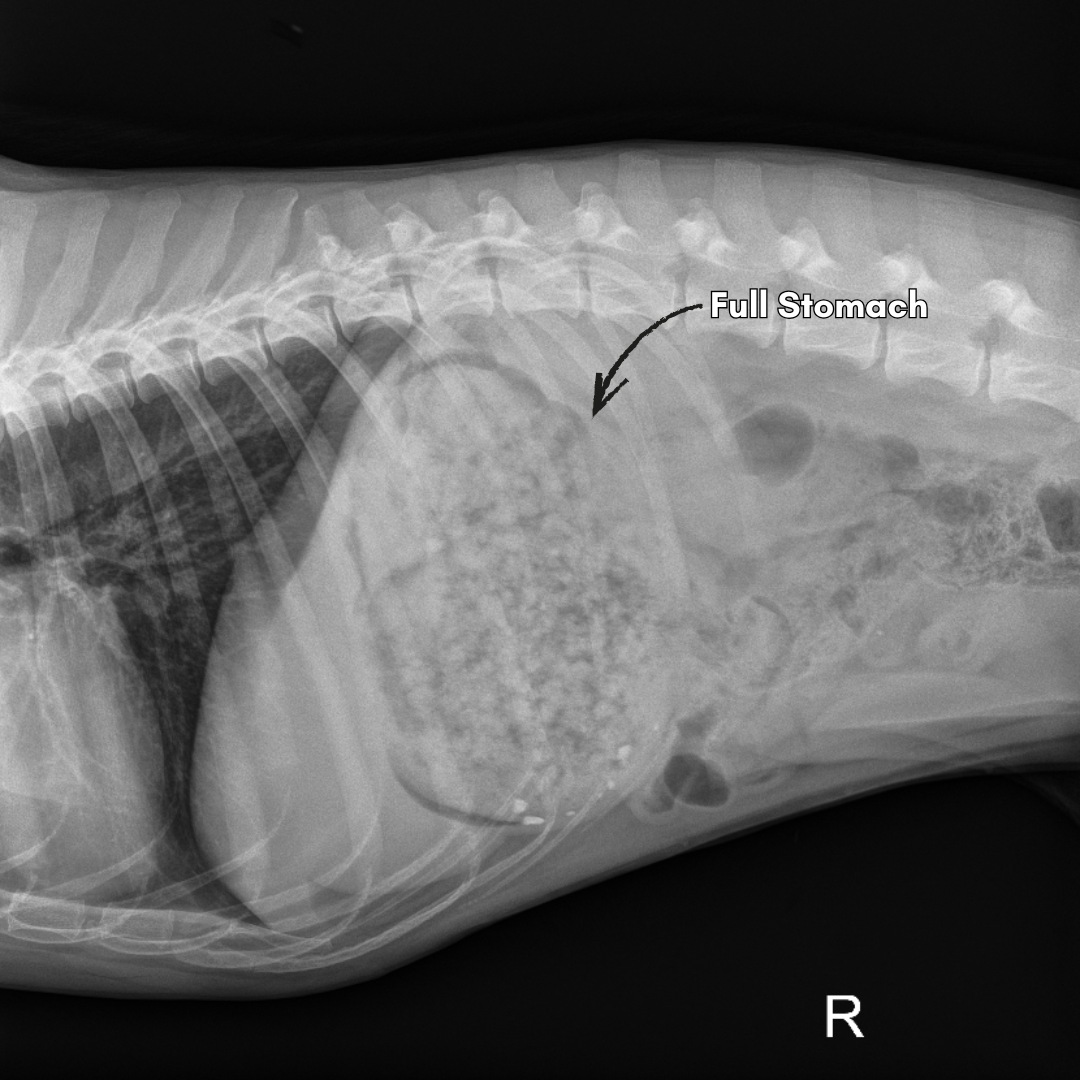

On physical examination, Tawny was dehydrated and seemed painful in her upper abdomen. I recommended taking an xray of her stomach and intestines to see if there was some sort of blockage present. The xray showed a very full stomach with what appeared to be some sort of granular material with some small bits of rocks present. There was also a lot of heterogeneous (grainy) material moving through her small and large intestines. A rectal exam revealed an empty rectum.

I recommended not feeding her for 24 hours and repeating an xray the following day to determine if the material had moved at all. I also gave her some fluids under the skin to help with hydration and an injection for nausea. I rechecked Tawny the following day and she was still not feeling well. The owner brought along a fecal sample since she had had a bowel movement and the contents were very strange. The feces was the consistency of a firm gummy worm and was very wide and black in color. The repeat xrays showed that the stomach contents had not moved at all. It was clear that whatever she had eaten at the barn had caused an obstruction in her stomach. Tawny was referred to the 24 hour hospital for a gastrotomy which is a surgery to open the stomach and remove the foreign material.